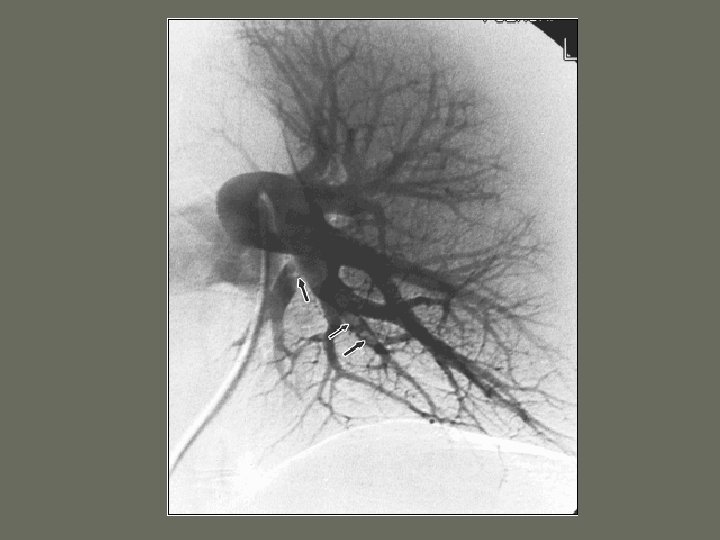

General Angiography Procedures 2. Pulmonary Angiography • Pulmonary _____

General Angiography Procedures 3. Abdominal Angiography • Branches off the abdominal _______